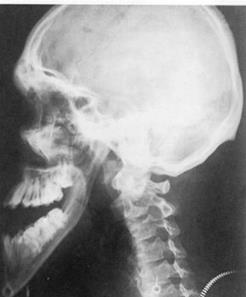

Az agyalapi mirigy elülső részének hiperfunkciója a növekedési időszakban gigantismust eredményez. Nemcsak a csontok, a lágyszövetek is növekednek. Acromegalia későbbi életkorban alakul ki, miután a csont epiphysisek összenőttek, a növekedési hormont termelő sejtek adenomája acromegaliát okoz. Ez ismételt növekedéssel jár, elsősorban az állkapcsokon, a kezeken és a lábakon. A porcok növekedési centruma is aktívvá válik, a mandibula megnagyobbodik és protrusióba kerül (16.2. ábra).

16.2. ábra. Acromegalia

(Cawson RA, Odell EW, Oral Pathology and Oral Medicine, Churchil-Livingstone, 2008)